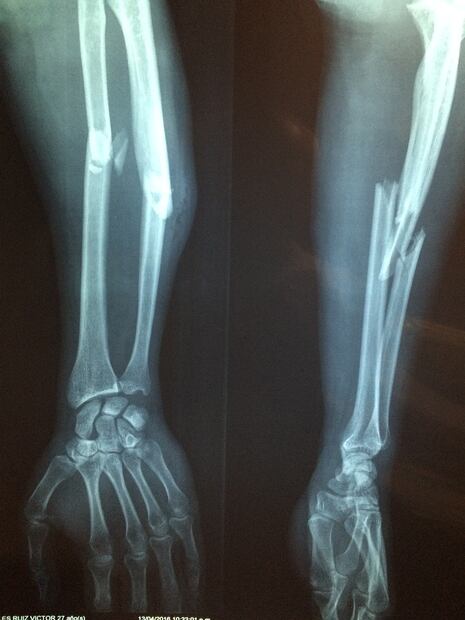

En este marco, uno de los temas de salud que más estudios ha demandado es la osteoporosis, una enfermedad que hace que los huesos se debiliten y se vuelvan frágiles, en tal medida que una caída o hasta una leve tensión, como agacharse o toser, pueden causar una fractura, según precisiones del Instituto Mayo Clinic.